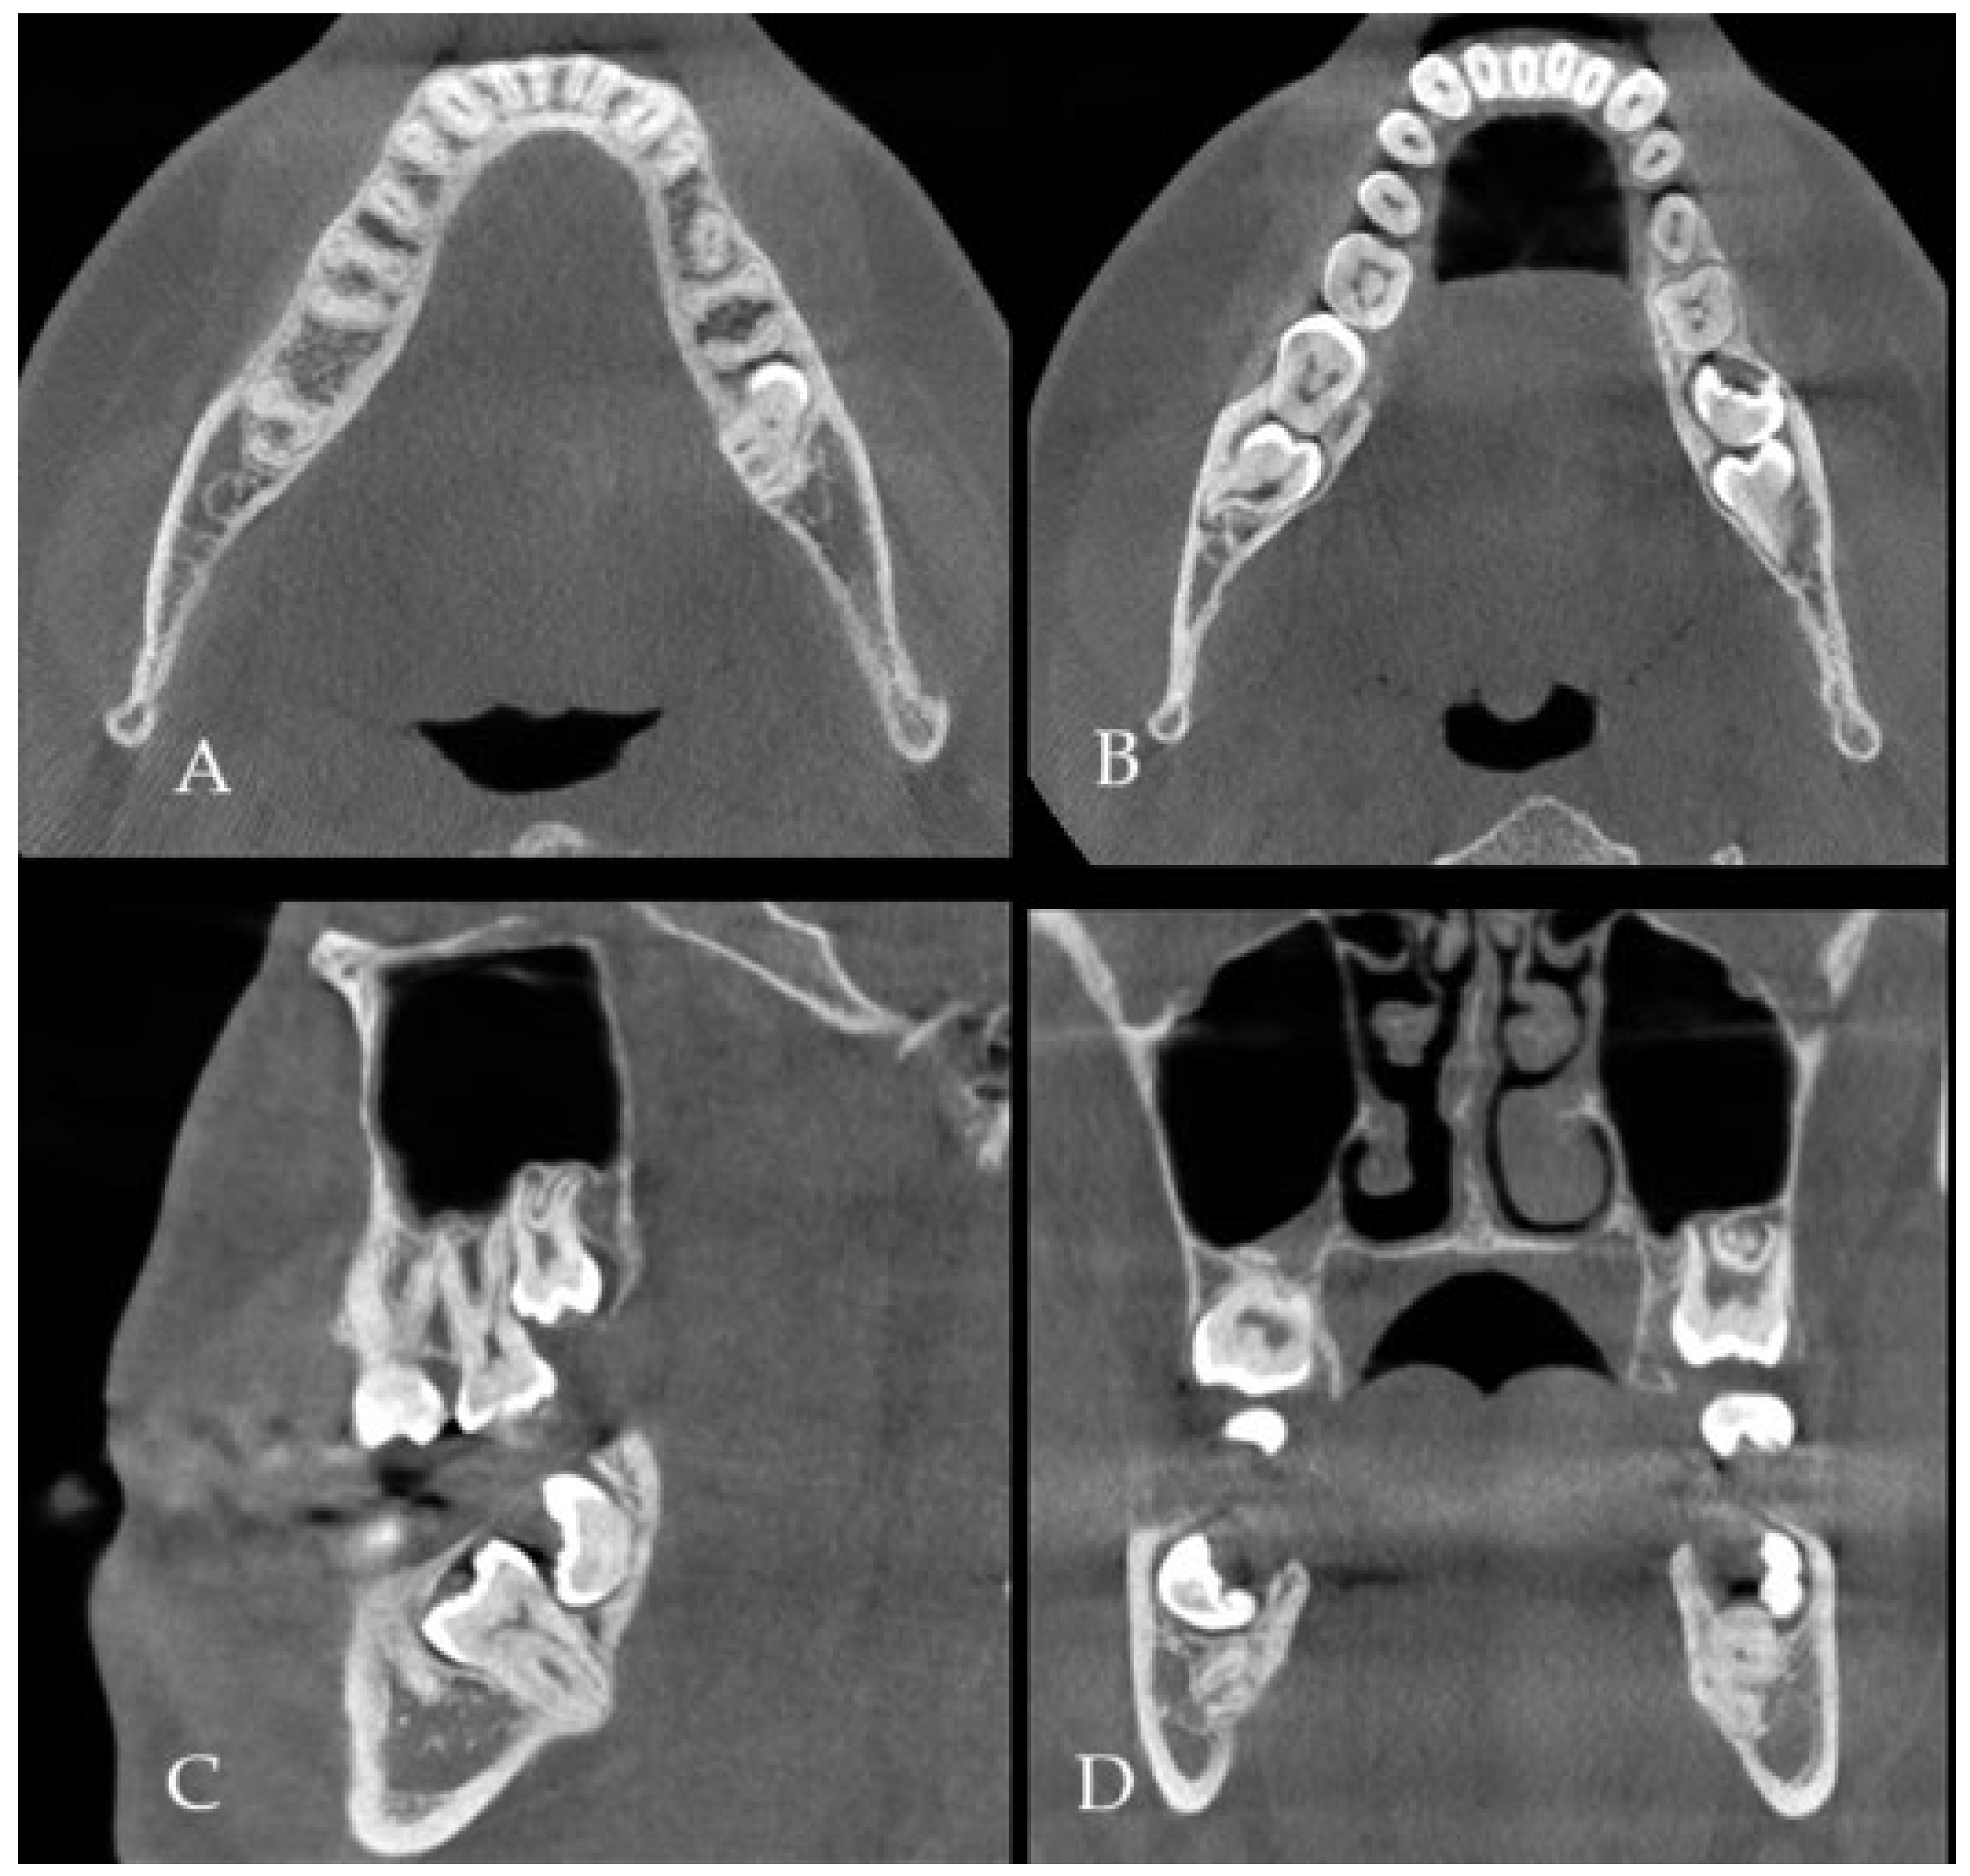

(A) CBCT (cone beam computed tomography scans: CBCT 20 × 20 cm FOV (field of view) imaging protocols based on RayScan S 5471.3 mGy (Ray Company Co., Ltd., Samsung 1-ro, Hwaseong-si, Gyeonggi-do, Republic of Korea), CBCT evaluation was carried out in RAYSCAN S without slicing, with an average thickness between 0.070 mm and 0.3 mm) is a very valuable diagnostic tool to estimate bone status, shape, and its anatomy, as well as the boundaries of the dentigerous cyst (DC) and impacted or retained teeth. The authors used a suitable software for CBCT evaluation (RadiAnt Dicom Viewer Software version 2020.2.1 Medixant, Poznań, Poland). In some cases, after the removal of any teeth and cysts or tumors within the jaw bones, it is quite common that due to the bone loss, a fracture of the mandible or some degree of bone mobility might be found. Some authors in those cases suggest not only a prophylactic bone plating with titanium miniplates but also applying some additional bone grafts to improve bone volume and avoid any early or late bone fracture. Both a bone fracture and its mobility after the removal of a certain portion of bone might not only cause its delayed healing, resulting in a complete or displaced fracture but also promote some granulation tissue, local inflammation, or fistula occurrence. A good CBCT evaluation is helpful in the planning of the scope of each surgery and in predicting the occurrence of some worrisome aspects, especially related to bone loss, fracture occurrence, and planning for any orthodontic treatment. The type of bone used (xenograft, allograft, autograft) could be used in various bone defects. In the presented case, because the occurrence of totally impacted teeth 37 and 38 with a presence of DC, a decision was made to use an allograft bone ((A–D), where (A,B) axial scans, (C)—sagittal view and (D)—coronal view in CBCT). Because of the level of teeth 37 retention, its proximity to the lower mandible border, and perforation of both lingual and buccal plates, a larger amount of bone was necessary to stabilize the mandible left basis deficit and improve its postoperative height and width. On the other hand, a so-called PMP (prophylactic/preventive mandible plating) during the removal of more locally advanced jaw lesions is a good solution. A panoramic radiograph (panx) or a classic CT does not show the close boundaries between tooth roots, inferior alveolar nerve (IAN), cortical plate, and the scope of DC occurrence, but the panx role for screening is quite good [1,2,3].